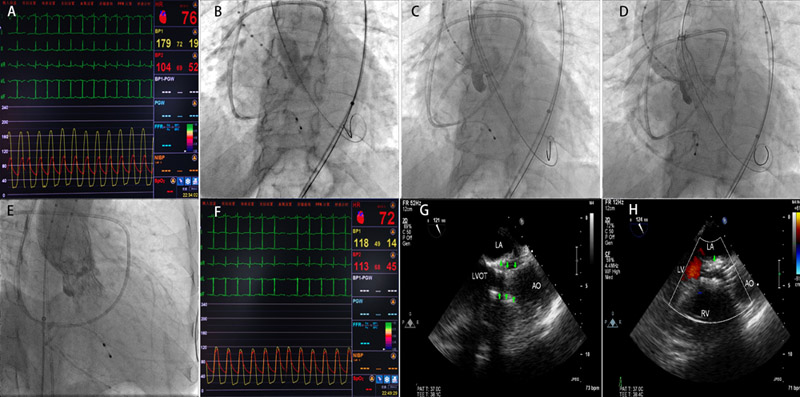

冠状动脉造影:前降支近中段及回旋支中段各有90%狭窄,右冠状动脉近段狭窄75%。分别于三支冠状动脉狭窄处置入药物洗脱支架各一枚。猪尾导管测量主动脉瓣跨瓣收缩压差75mmHg(图2A)。18mm x 30mm球囊预扩主动脉瓣(图2B),18F输送鞘置入26mm Medtronic自展人工支架瓣膜(图2C、D、E)。导管测量无明显跨瓣压差(图2F),造影及超声评估微量主动脉瓣返流(图2G、H)。

图2:A:术前跨主动脉瓣压差;B:18mm球囊预扩张;C:18F输送鞘开始置入26mm自展式人工主动脉瓣;D:自展式人工主动脉瓣释放前;E:自展式人工主动脉瓣释放后造影;F:术后跨主动脉瓣压差;G:置入瓣膜后食道超声支架影像(绿色箭头);H:置入瓣膜后食道超声瓣膜无明显返流。